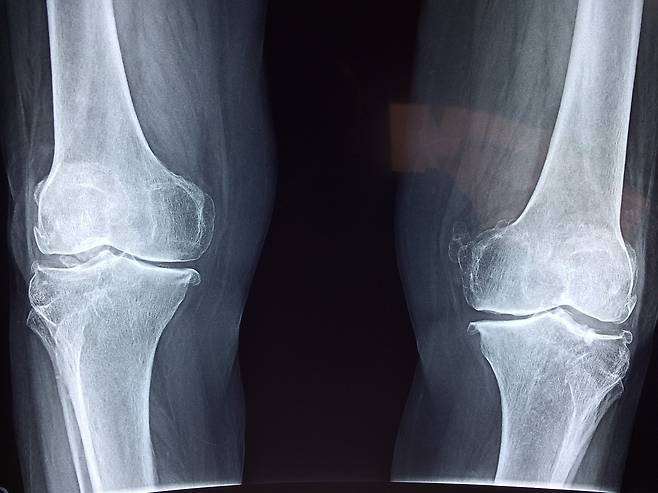

4)관절 보호

허벅지 근육은 무릎과 고관절에 가해지는 부담을 줄여주는 역할을 합니다.

근육이 충분히 발달하면, 하체의 근육이 관절을 지탱하고 보호하는 데 중요한 역할을 하여, 관절 질환의 위험을 감소시킵니다.

특히 무릎 관절염과 같은 문제를 예방하는 데 도움을 줍니다.

하체 근육이 약해지면 관절에 더 많은 부담이 가해지므로, 허벅지 근육을 강화하는 것이 관절 건강에 중요합니다.